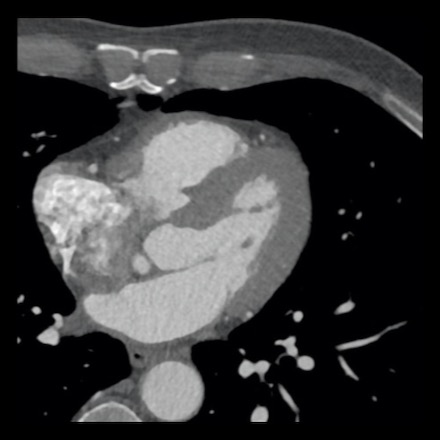

case 4 – CAD-RADS 3/P1/I+ thrombus left ventricle

First, scroll through the CTA images.

How would you describe the findings on the coronary CTA?

The findings are:

- Moderate (50-69%)

stenosis in the proximal LAD caused by a non-calcified plaque. - Variant of

sinoatrial (SA) nodal artery. The artery usually arises from the RCA as a second

branch after the conus artery, however in this case it arises from the LCX,

courses behind the aorta, anastomosing with the right atrium and with a small

branch supplies the SA-node of the heart. - Thrombus in the

apex of the left ventricle. - CTP was performed

in this patient. CTP showed a perfusion defect at stress imaging in the

territory of the LAD (I+), at rest no perfusion defect was visible.

This patient classifies as CAD-RADS 3/P1/I+, which means

this patient requires further investigation.